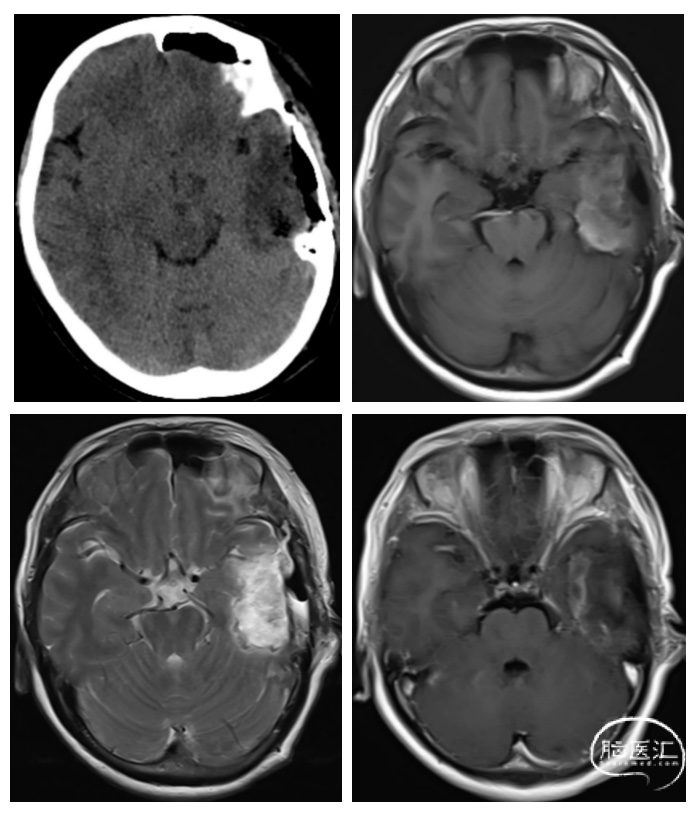

术前影像学检查:术前头颅CT及MR影像(图1)显示:CT提示左侧颞叶低密度病灶,边界欠清;MR提示左颞叶病灶呈长T1长T2信号影,边界欠清,呈脑回样肿胀表现,伴周围多发空泡状长T2信号小结节影,增强后强化不明显;MRS提示NAA下降,Cho升高,Cho/NAA=1.85,Cho/Cr=1.83。

图1.术前头颅CT及MR检查,可见左颞叶占位,长T1长T2信号影,增强后强化不明显,MRS提示肿瘤病变。